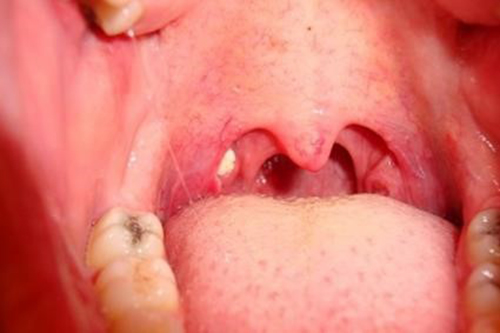

편도염은 인후 감염으로 편도선 주위에 염증이 발생되는 경우입니다. 편도선염 이후에 편도선에 자리가 남아 그곳에 편도결석이 생기기도 합니다.

편도선은 인후 양쪽에 위치해 있어 호흡기 감염을 예방합니다. 그러나 편도선은 다른 감염으로 몸을 지키지만 그 자체가 쉽게 감염이 됩니다. 그렇기 때문에 많은 분이 감기 초기 증상은 인후통으로 편도선 부위가 심하게 붓기 시작합니다.

편도선이 부으면 인후통, 목 가려움, 귀앓이, 발열 및 오한 등이 동반됩니다. 또한 목고 마시는 것이 매우 힘들어집니다. 심지어 침만 삼켜도 고통을 호소합니다.